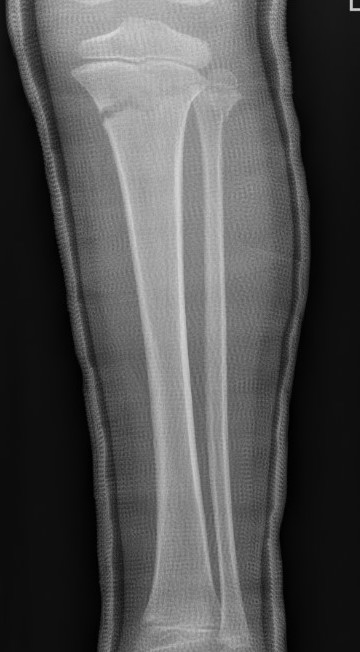

Proximal metaphyseal tibial fracture

Cozen phenomenon

Delayed valgus deformity secondary to medial tibial elongation

Valgus malalignment